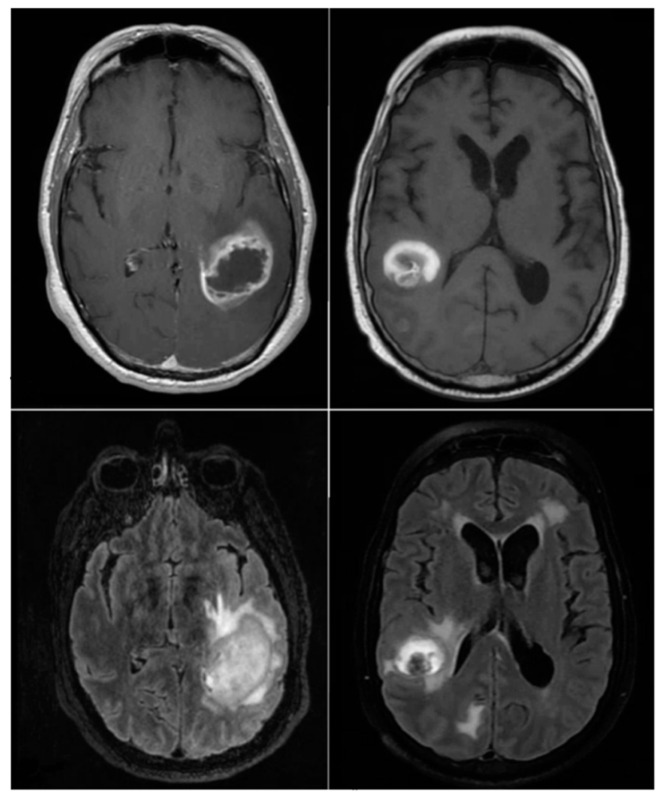

Methods: We analyzed magnetic resonance imaging scans from 19 brain metastases patients, focusing on axial fluid-attenuated inversion recovery and high-resolution contrast-enhanced T1-weighted sequences. Patients were categorized into responders (complete or partial response) and non-responders (stable or progressive disease).

Abstract Image